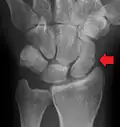

-

A subtle scaphoid fracture -

A more obvious scaphoid fracture on a scaphoid view X ray -

Radiolucency around a 12 days old scaphoid fracture that was initially barely visible.[13]